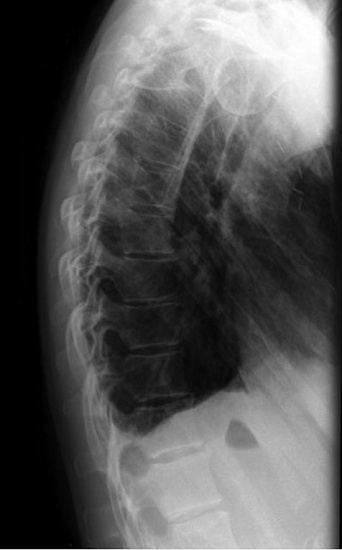

1. Рентгенография органов грудной клетки в 2-х проекциях - скрининговое исследование органов грудной клетки, выполняемое в двух проекциях.